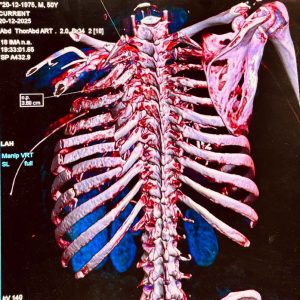

After several days of careful monitoring and preparation, a major and highly complex surgery was undertaken on December 25. A multidisciplinary team performed an open chest operation to repair the torn lung and reconstruct the shattered rib cage on the left side. The procedure was technically rare and demanding, requiring surgeons to approach the ribs from the posterior aspect of the chest, close to the spine, a route that offers direct access but demands exceptional precision. In areas where the ribs were too damaged to hold standard screws, the surgeons improvised by fixing a specially shaped metal plate to the transverse process of the T5 vertebra to stabilise the chest wall. “This was an innovative and bold decision taken in the operating theatre. It restored chest stability, stopped the dangerous inward collapse of the chest, and allowed the lung to re-expand,” an AIIMS Kalyani official said.

The surgery was led by two eminent doctors – Pranay Kabiraj and Debmoy Ghatak, with assistance by other doctors like Manoj Kumar and Pulkit, while anaesthesia was managed by Aziz and Anuja. Hospital records show that multiple pre-shaped plates and locking screws were used to rebuild the rib cage, followed by meticulous lung repair, thorough cleaning of the chest cavity, layered closure and placement of drains. “The scale of reconstruction reflected both the severity of the injuries and our resolve to provide advanced trauma care here itself, without forcing families to travel far,” an AIIMS Kalyani official stated.